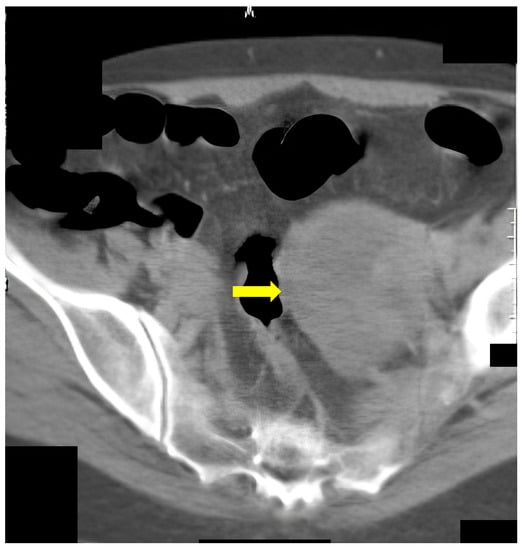

The last example of our experience is a 67-year-old male (Figure 7) who underwent incomplete fibrocolonoscopy, which was not completed because of stenosis of the intestinal lumen due to functional transitional spasm. Afterward, CT colonography was performed, which showed carcinoma of the stomach with metastasis in the liver.

Figure 7.

A 67-year-old patient. CT scan, axial view. Incomplete FCS with suspicion of functional spasm. Normal intraluminal view on FCS. After CT colonography, a stomach carcinoma with liver metastases was found (yellow arrow).